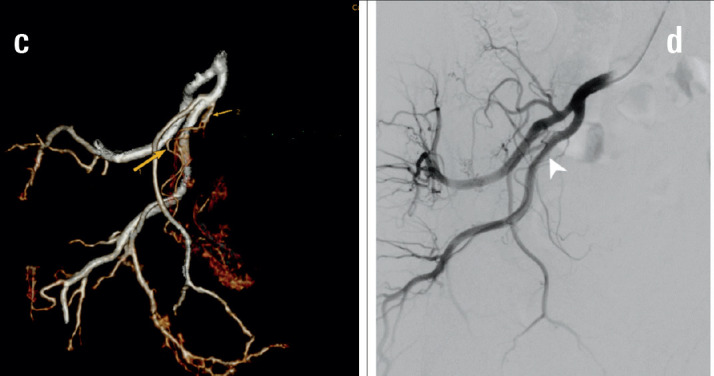

Objective: The study aimed to describe the anatomy and imaging findings of the prostatic artery (PAs) on 3D rendering dual-energy multi-sequence computed tomography (DECT) in patients with symptomatic benign prostatic hypertrophy (BPH) treated by prostatic artery embolisation (PAE).

Methods: The study was conducted on 64 patients with BPH who underwent DECT scans with 3D rendering of the pelvic artery before intervention from August 2022 to November 2023. The PAs were independently evaluated for each side, focusing on the number of branches, origin, tortuosity, atherosclerotic plaque, and anastomoses with adjacent arteries.

Results: Among 128 pelvic sides where the PAs can be observed, the rate of finding 01 prostate artery on each side was high (96.1%), and the rate of 02 prostate arteries on each side was rare (3.9%). In 133 prostatic arteries, the most common type of prostatic artery according to origin is type I (29.6%), followed by type III (24.6%). The atherosclerotic prostatic artery rate is 24.6%, and the average diameter is 1.5±0.4 mm. The tortuosity prostate artery accounted for 74.6%. The anastomosis to the contralateral prostatic artery rate is 48.4%, followed by the penis and rectum anastomoses.

Conclusion: PAs have abundant original varies between the left and right sides and between patient to patient. The most common form arises from the internal pudendal artery.